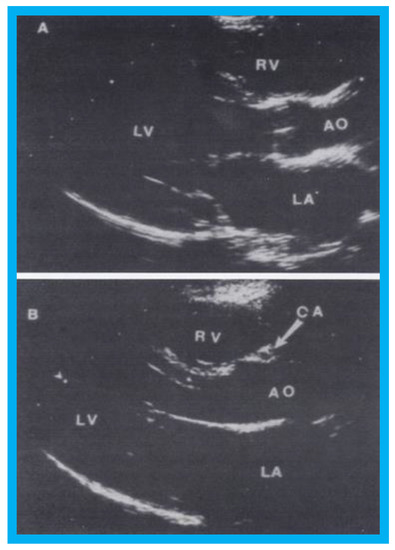

Figure 12. Selected video frames from parasternal long-axis view in a normal child (A) and in a child with aberrant coronary artery (B): Note a cross-sectional image of the coronary artery (CA) is seen in (B) in the anterior wall of the aorta (AO) while such is not seen in (A). LA, left atrium; LV, left ventricle; RV, right ventricle. Reproduced from Jureidini S.B., et al. [15].